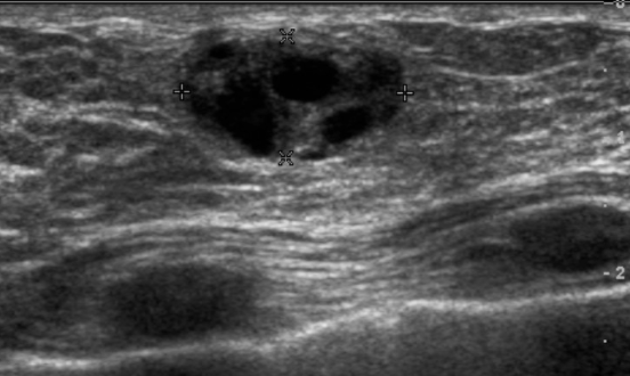

What is a simple cyst?

benign breast condition

Very common in women ages 35 to 50

Results from obstructed duct or hormonal changes

Regress after menopause

Presentation: breast lump, pain & tenderness

What is the Sonographic Appearance of simple cysts?

Oval or round

anechoic

smooth walls

well circumscribed shape

posterior enhancement

edge refraction

sharp anterior and posterior borders

reverberation